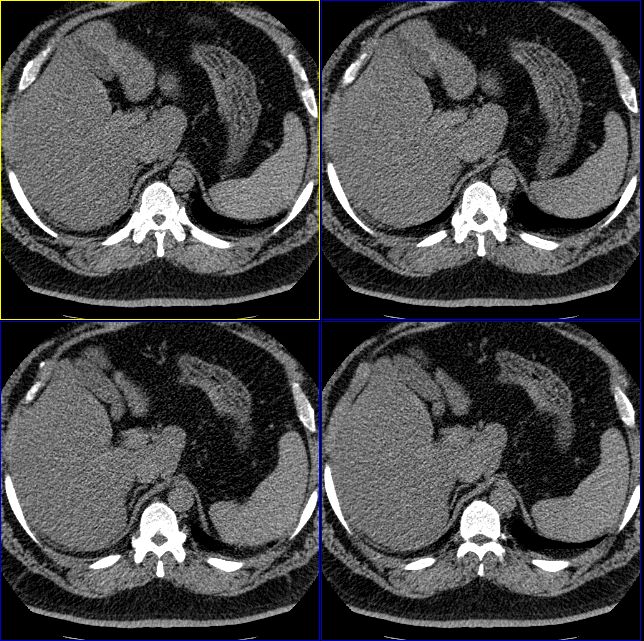

男性,37岁。体型极度肥胖,达300余斤。

支持脂肪肝,从图象看脾的密度要高于肝的

肝脏密度普遍减低,从图象看低于脾脏,支持脂肪肝。

脾v扩张、迂曲 脂肪肝,早期肝硬化

轻度弥漫性脂肪肝。